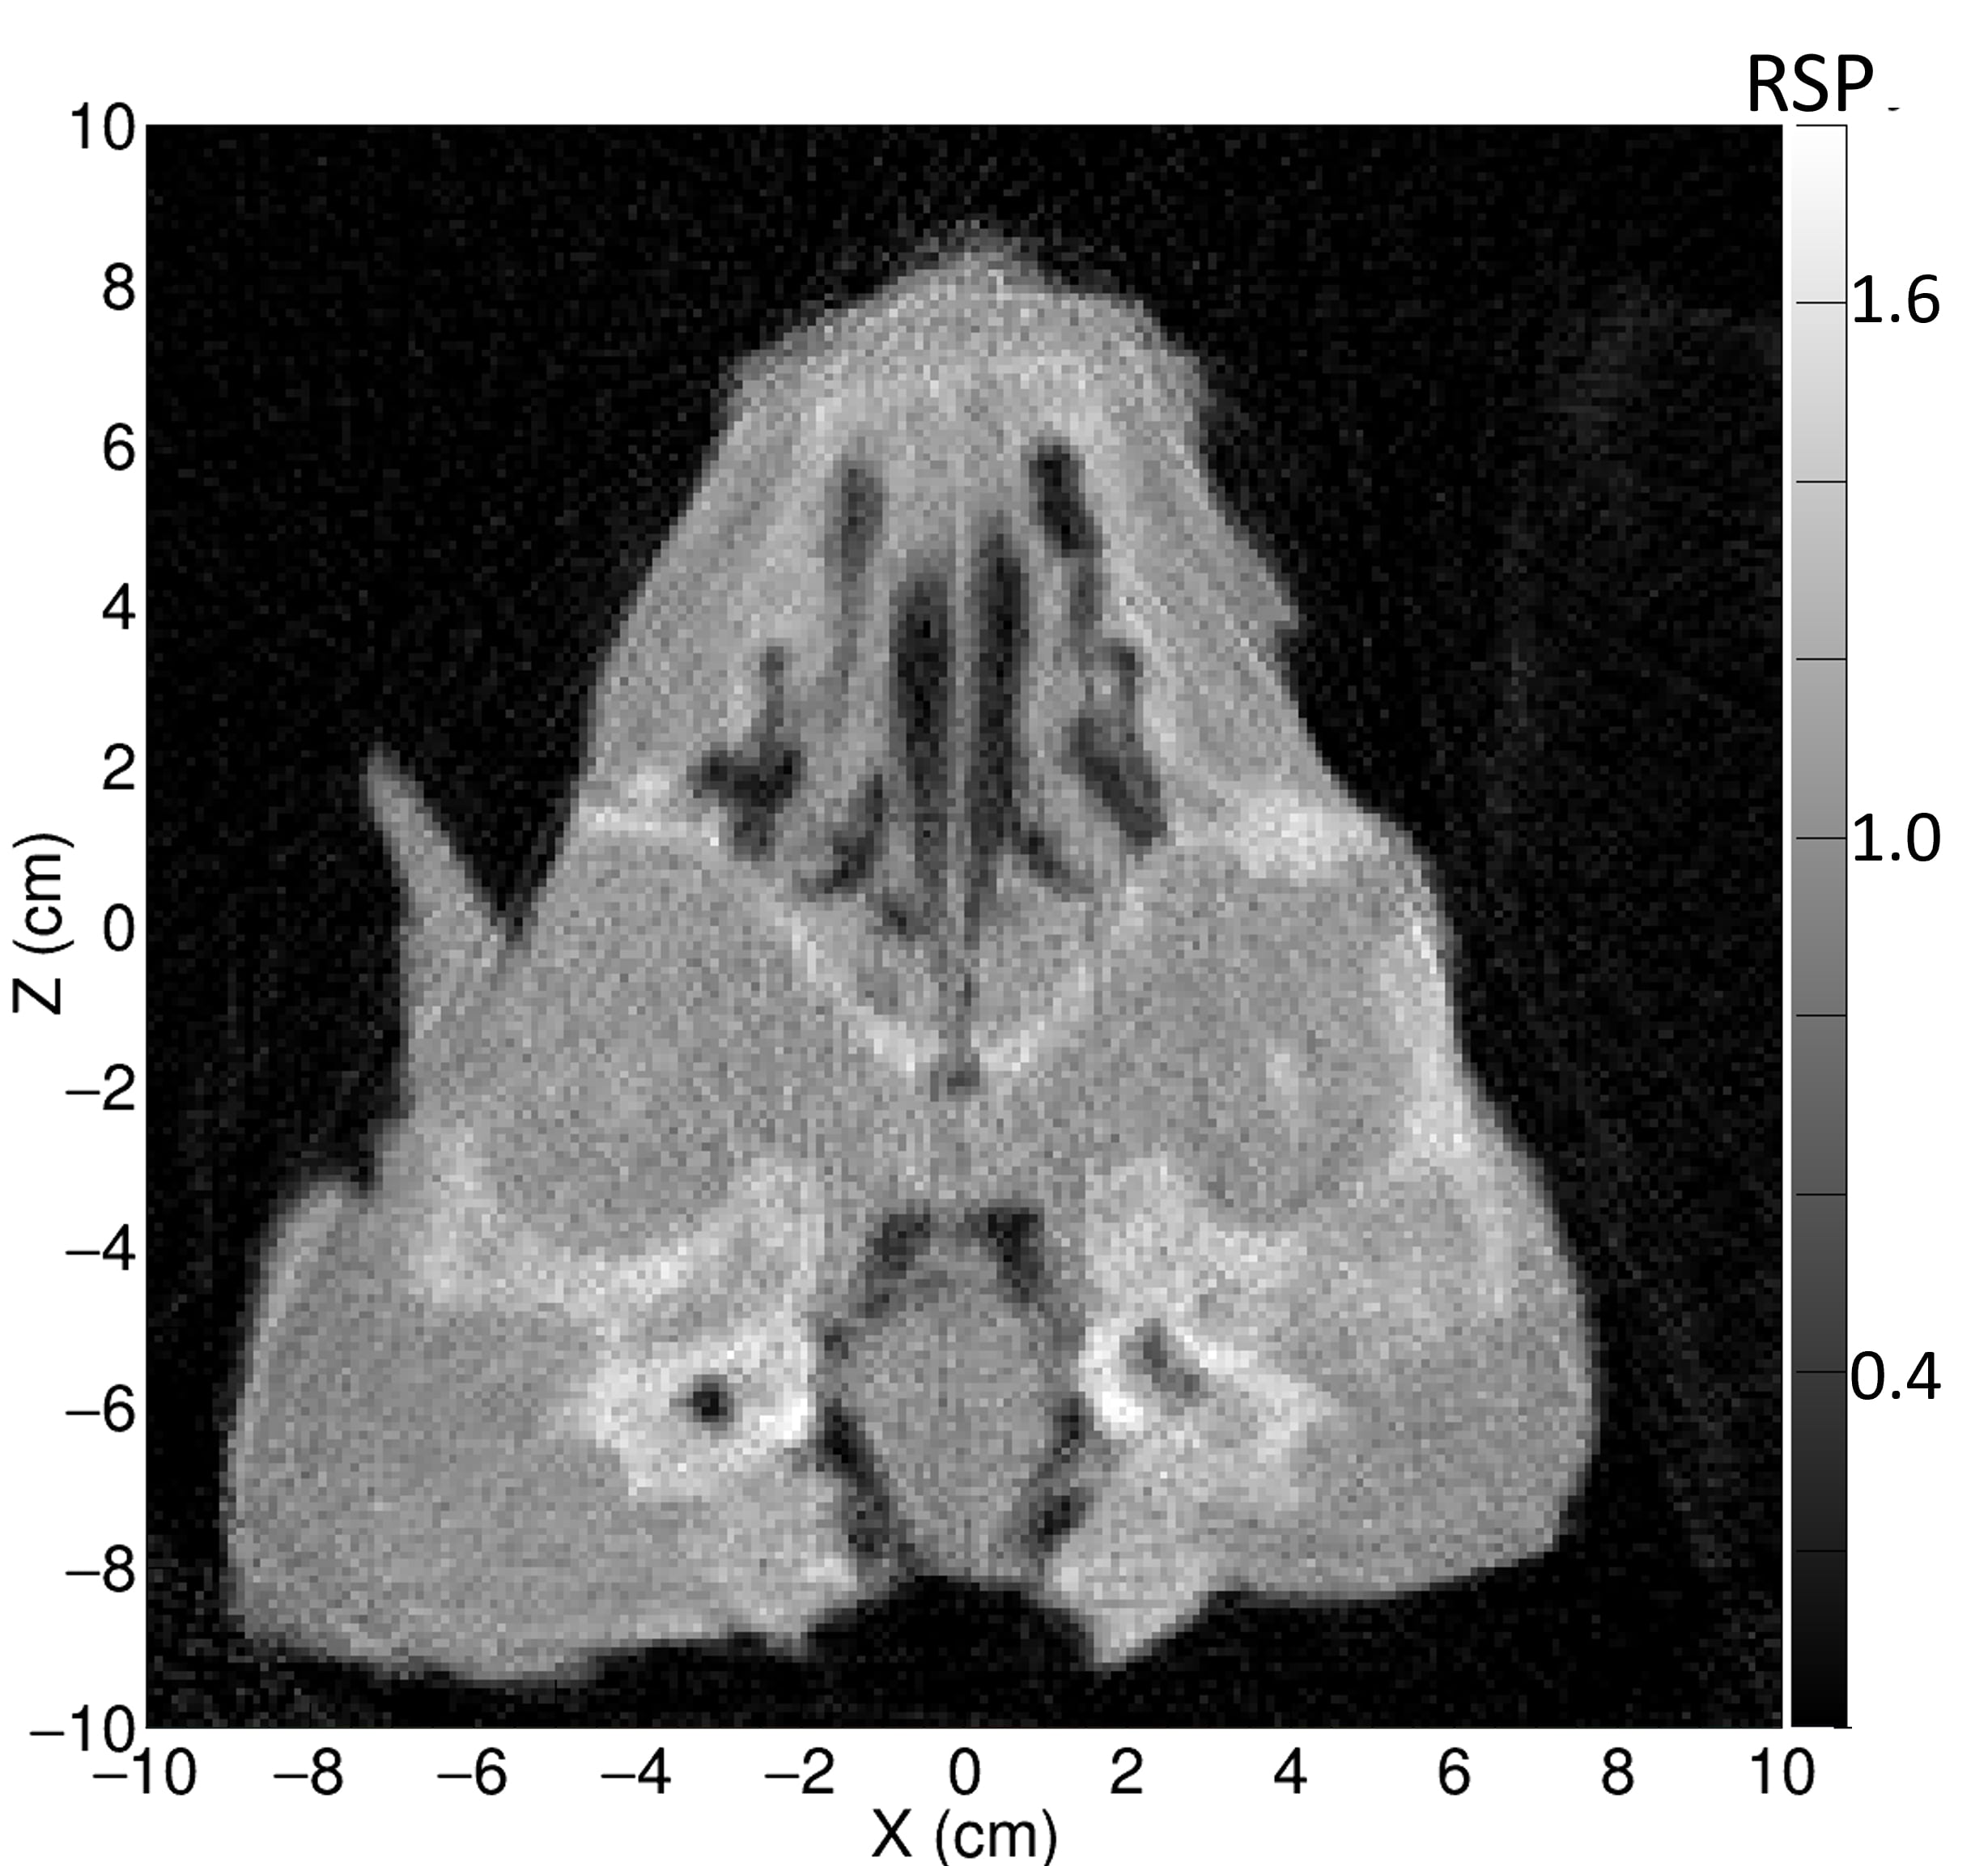

3.D. Comparison of pCT and x-ray CT for the pig’s head

Examples of regions for one slice each in three views of the pig’s head are indicated in Fig. 6, and RSP comparisons between the pCT and the three x-ray CT scans are in Table 3. A close up axial view of the tympanic bullae is shown in Fig 7, which illustrates that the tympanic bullae ROI encompasses a heterogeneous mixture of pneumatized cells separated by thin bony septa. The high and low dose horizontal CT RSPs are consistent within 0.5%. The vertical x-ray CT scan generally shows similar results, although with differences of 2% for brain stem and skull relative to the horizontal scans. Ignoring the RSP differences for sinus air, which are insignificant in absolute terms, the largest difference between pCT and x-ray CT is for the bullae, (-29% to -41%), followed by skull (-2.4% to -4.3%) and brain stem (-2.2% to -4.4%). All other RSP differences (n=24 for 8 tissues) range from -2.5% to +2.1% with a mean of -0.4%. With the exceptions of tongue and lens, the differences for these eight tissues are negative or zero.

Fig. 8 shows a comparison of the average of ten 1 mm sagittal slices from a lateral region of the pig’s head for pCT and the vertical x-ray CT, in order to reduce noise. Features are slightly blurred due to their change in shape with depth. The grey scale reflects the measured RSP, whereas in Fig. 6 and 7 the grey scales were windowed and levelled to optimize contouring. The largest differences are in regions of heterogeneity such as the teeth and tympanic bullae.

The difference map also clearly shows the systematic discrepancy in the skull and the mandible, while soft tissue regions such as brain and muscle regions show closer agreement. The difference in the tip of the snout is caused by an incomplete set of pCT data through that area. The pencil beam scans used for the pCT data set only covered a cm2 area, so the tip of the snout was not quite covered at lateral angles.